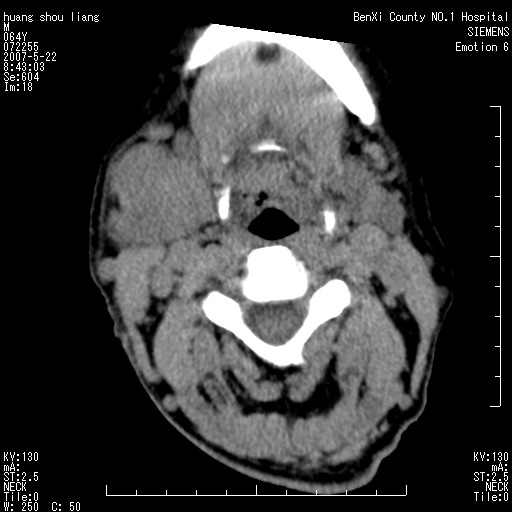

男性,64岁。颈部包块8年。最近增大。

对不起大家,可能是片子发太多有点乱,正常腮腺在下颌角的外侧,颌下腺在下颌体的中部内侧,本例在下颌角内侧偏下,和腺体一点关系都没有,从vrt和mpr上可以很明显看出来,再者肿块是好多粘连在一块的,大家在仔细看看,左侧可能也是吧,我还是考虑为肿大的淋巴结融合在一块,但性质??????

右侧腮腺下部均匀软组织密度肿块,外形不规则,与周围组织分界清晰,考虑右侧腮腺混合瘤或多形性腺瘤。

大家好,病理结果出来了,如大家所说,颌下腺混合瘤。

唉,解剖没学好吧,我诊断错了,不过还是有些不理解回去我在多看看书,谢谢大家的参与,以后我还会奉献好的病例。